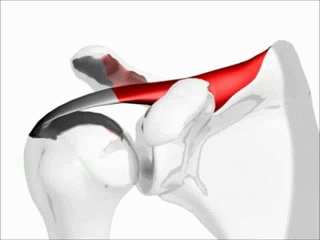

오십견은 관절주머니에 염증이 생기거나 뻣뻣해지면서 비정상적인 조직이 관절면 사이에 자라나 발생하며, 통증과 관절의 움직임 제한을 일으킨다.[8]슬랩 파열(SLAP tear영어)은 오목테두리의 파열이 원인이다. 특정 위치에 어깨 통증이 발생하고, 테니스나 던지는 동작이 있는 스포츠와 관련된 통증, 어깨 쇠약 등의 증상이 나타난다. 수술로 복구해야 하는 경우도 종종 있다.[8]

돌림근띠의 힘줄과 그 근육들(가시위근, 가시아래근, 작은원근, 어깨밑근)은 어깨관절을 안정하게 하고 고정시킨다.[4] 가시위근은 어깨관절을 처음 15도까지 벌리는 역할을 하고, 가시아래근과 작은원근은 벌림과 바깥쪽돌림을 돕는다.[6]